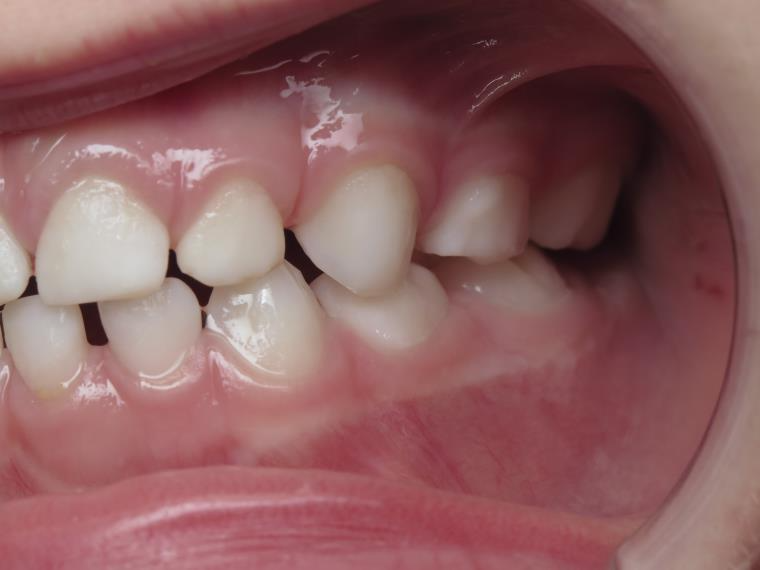

7.inversé droit 4 ans

inversion des dents postérieur coté droit

bilan début et en cours de traitement